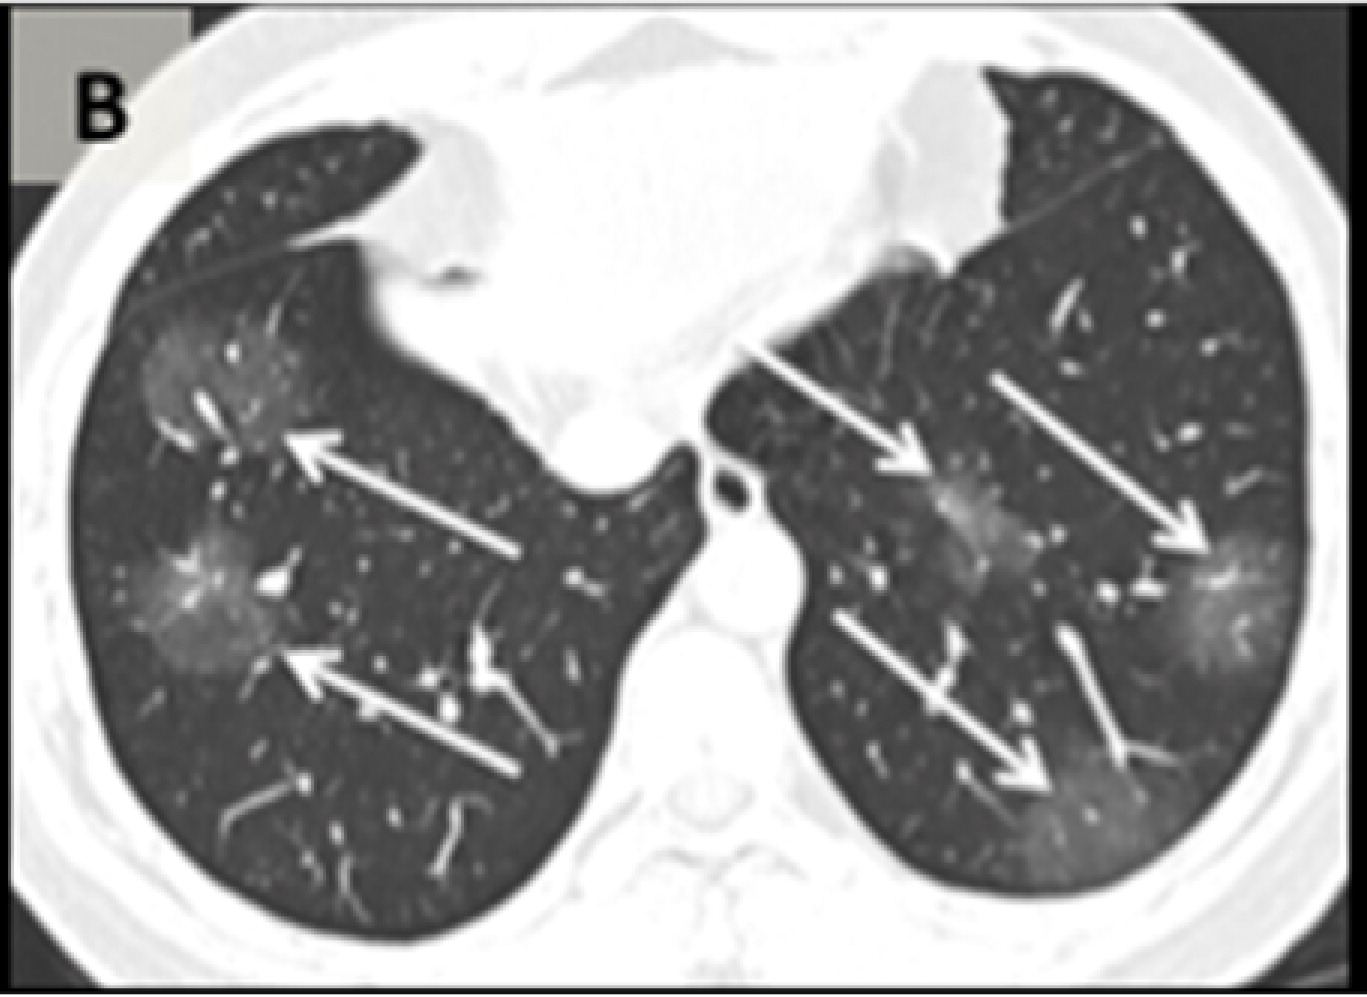

Матовое стекло коронавирус кт

Снимки легких кт коронавируса

Коронавирусная пневмония на кт

Пневмония коронавирус кт

Коронавирусная пневмония на кт

Кт легких пневмония коронавирус

Пневмония кт матовое стекло

Фото рентгеновских снимков поражения легких при COVID-19

На фотографиях рентгеновских снимков видно, как вирус воздействует на легочную ткань. Характерные признаки поражения легких включают пятна, инфильтраты и наличие жидкости внутри легочных альвеол.

Фото рентгеновских снимков помогают врачам и специалистам визуально определить степень поражения легких и принять соответствующие меры лечения и поддержки пациента.